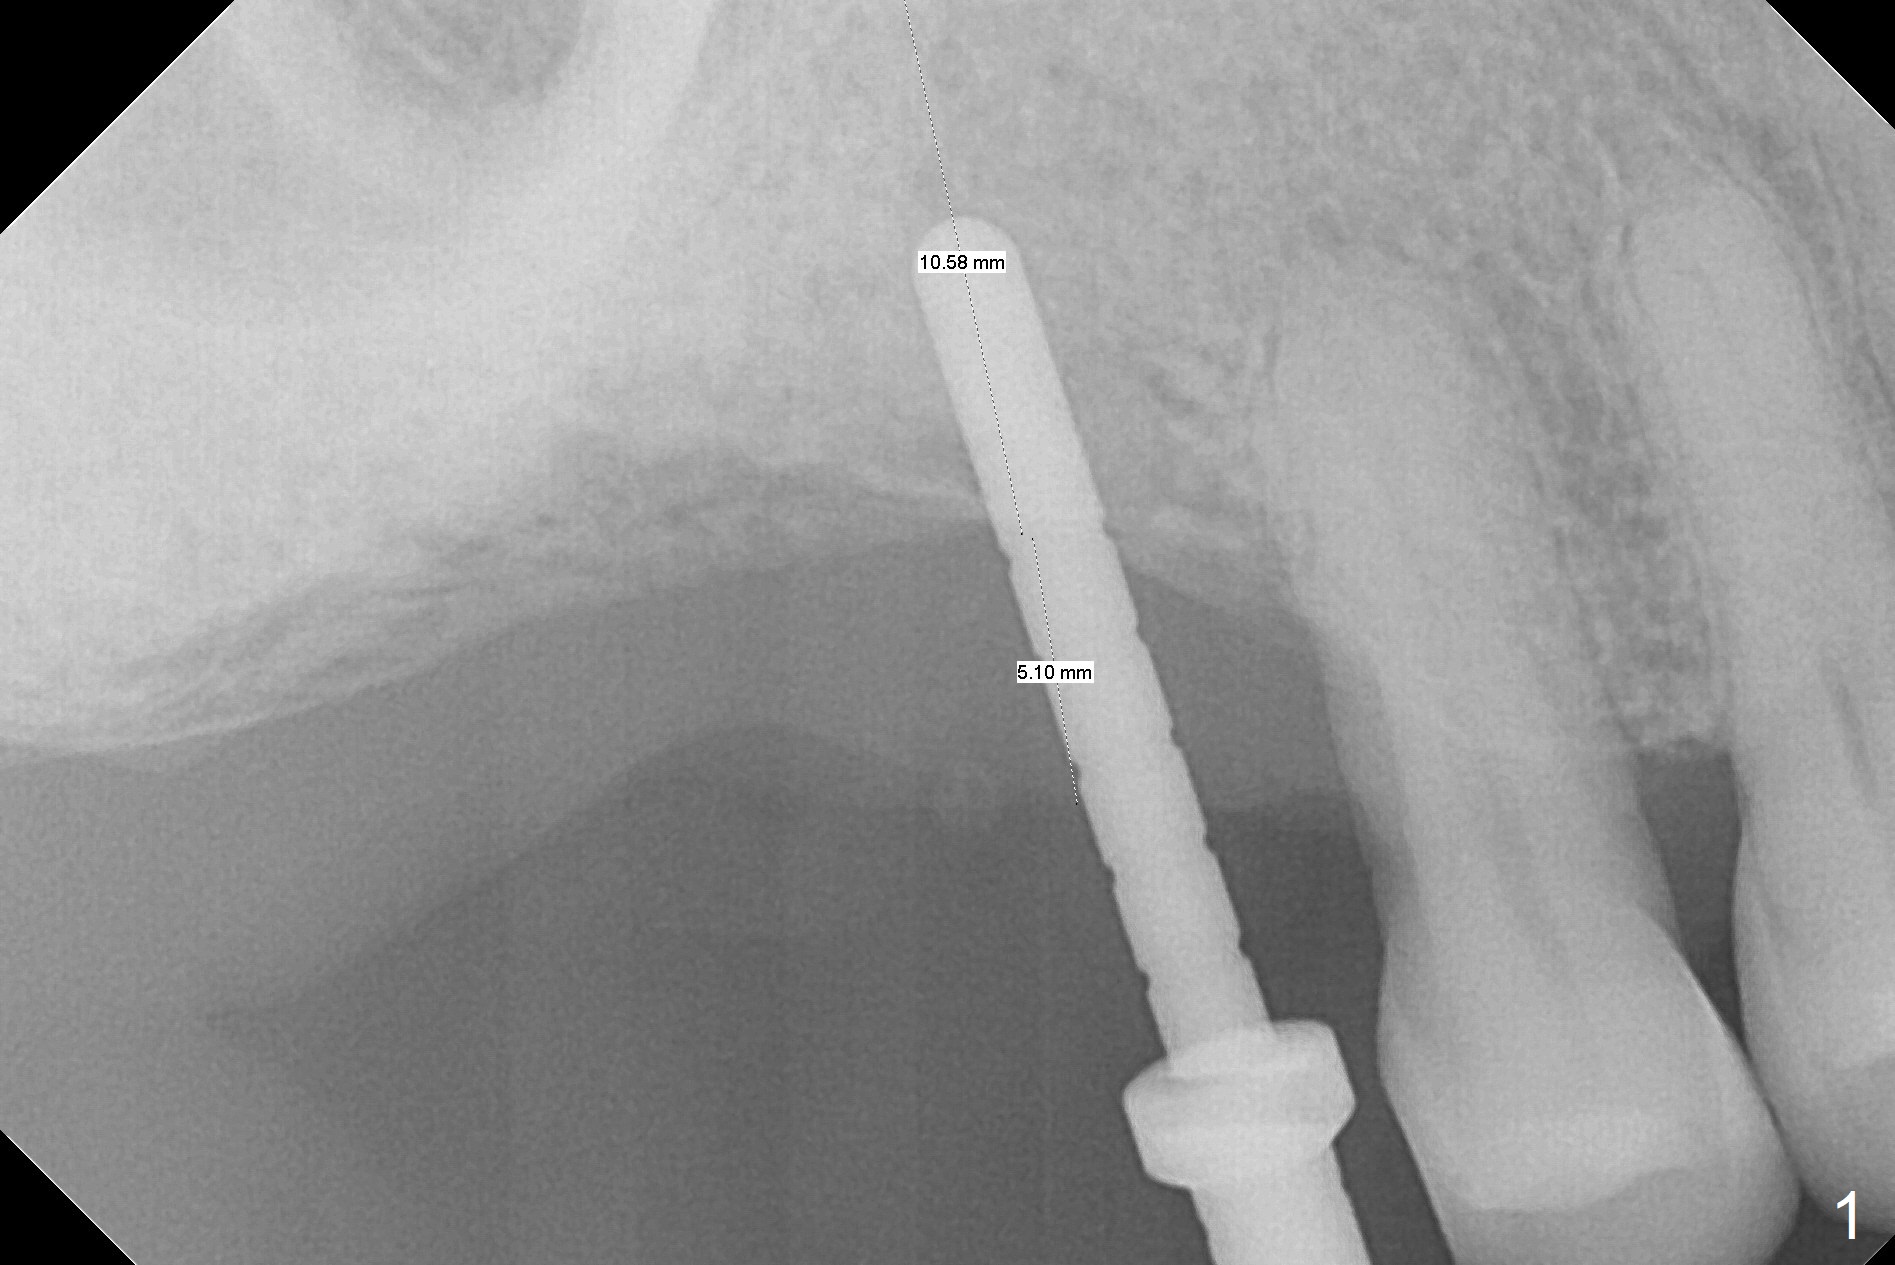

Since the ridge crest at #3 is narrow, Tatum bone scalpels are used to get access and initiate bone expansion, followed by bone blades and RT 2. It seems that the osteotomy starts mesially; bone height being increased (Fig.1). When the apical end of the osteotomy tilts mesially, more bone height is obtained. Drills are alternatively applied because of the hard bone (Fig.2). A 4x13 mm UF implant is placed initially with the distal threads unburied (Fig.3, >50 Ncm). With further seating of the implant, a 5.5x5(4) mm abutment is used (Fig.4), which closes the access. No suture is warranted. An immediate provisional is fabricated for the patient's comfort and psychological effect. In fact, the abutment cuff changes to 5 mm prior to temporarization. There appears no bone loss <4 months postop (Fig.5). Pulpitis develops at #4 due to DO caries 1 year 5 months post cementation (Fig.6 *). The crown at #3 is removed for easy and conservative distal carious removal and Cavit temporary restoration to prevent sodium hypochlorite leakage. Then occlusal access is made for pulpotomy. When RCT finishes, no crown will be made, but occlusal reduction is required. The patient returns for RCT 1 month later (Fig.7,8). Cavit remains in place (Fig.7 C). Although 2 threads are exposed distal (Fig.8 arrow), there is no sign or symptom of periimplantitis, which may be related to the thick gingiva (arrowhead). Return to Upper Molar Immediate Implant, IBS, #14 (Tissue Punch) Xin Wei, DDS, PhD, MS 1st edition 08/25/2017, last revision 09/08/2019